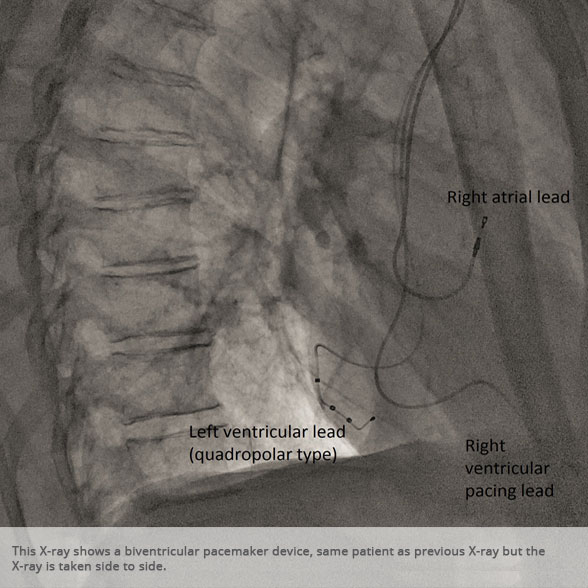

Biventricular pacemaker device Biventricular pacemaker device

Above: Slideshow containing X-rays of common medical procedures.

BI-VENTRICULAR PACEMAKERS

Bi-ventricular pacemakers are used for the treatment of suitable patients with heart failure who are already on medication but who suffer from a lack of synchrony between the right and left ventricular contraction. This is most commonly caused by an electrical delay (left bundle branch block LBBB) in transmission of signals to the main pumping chamber (called the left ventricle) and is relatively common in patients with advanced heart failure. This delay process commonly worsens the symptoms of heart failure and it is not generally influenced by medication alone.

Although not all patients universally respond to bi-ventricular pacing (or cardiac resynchronisation therapy/CRT), patients with more advanced dys-synchrony tend to experience remarkable improvement. Bi-ventricular ICDs have the additional benefit of recognising life threatening arrhythmia and deliver both fast pacing bursts or shocks to restore normal heart rhythm.